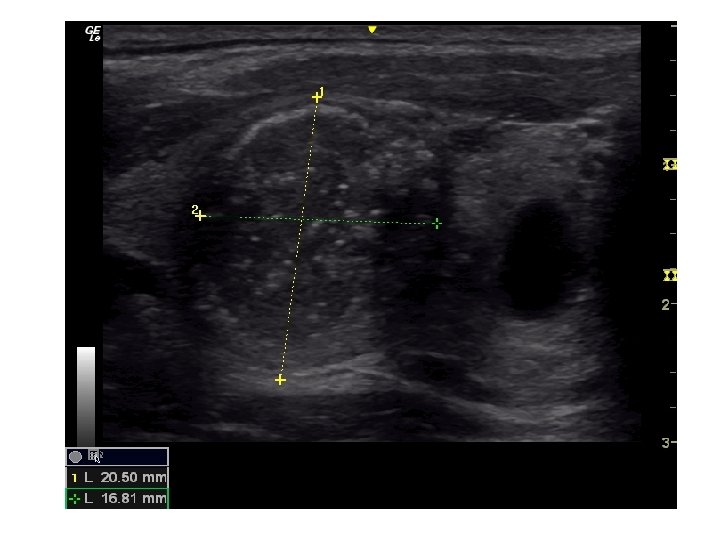

• Tiroid USG • Klinik olarak veya • diğer görüntüleme yöntemlerinde saptanan nodülün tanısının konması için gerçekleştirilir. • USG nodülün – – – – – Boyutu Lokalizasyonu İçeriği Kenar düzeni, Kalsifikasyon varlığı, Ekojenite, Vaskülarite, Şeklinin ve Lenf nodüllerinin değerlendirilmesi için kullanılır.

Sonografik Özellikler, Tahmini Malignite Riski ve İİAB Önerileri Sonografik patern US özellikleri Tahmini Biyopsi için önerilen çap malignite riski >%70 -90 >1 cm Yüksek risk Solid hipoekoik nodül veya solid hipoekoik komponenti bulunan parsiyel kistik nodül: düzensiz sınırlar (infiltratif, mikrolobüle, dikensi), mikrokalsifikasyonlar, boyun enden daha uzun olması, çevrede hipoekoik yumuşak doku komponenti bulunan bozulmuş çevresel kalsifikasyon alanları, tiroid dışına uzanımın kanıtı Orta risk Mikrokalsifikasyon, tiroid dışı uzanım ve uzunlamasına şekil içermeyen düzgün sınırlı hipoekoik solid nodüller %10 -20 >1 cm Düşük risk Mikrokalsifikasyon, tiroid dışı uzanım ve uzunlamasına şekil içermeyen düzgün sınırlı izoekoik/hiperekoik solid nodül veya kenarında uniform solid alanlar içeren kısmen kistik nodül %5 -10 >1. 5 cm Çok düşük risk Ultrasonografik olarak yüksek, orta veya düşük risk tanımlamaları içinde yer almayan spongioform veya kısmen kistik nodüller <%3 >2 cm yapılabilir İİAB yapılmadan izlem de makul bir seçenektir Benign Pür kistik nodüller (Solid komponent yok) <%1 Biyopsi gereksiz( Kist aspirasyonu, semptomlara yönelik veya kozmetik amaçlı planlanabilir. )